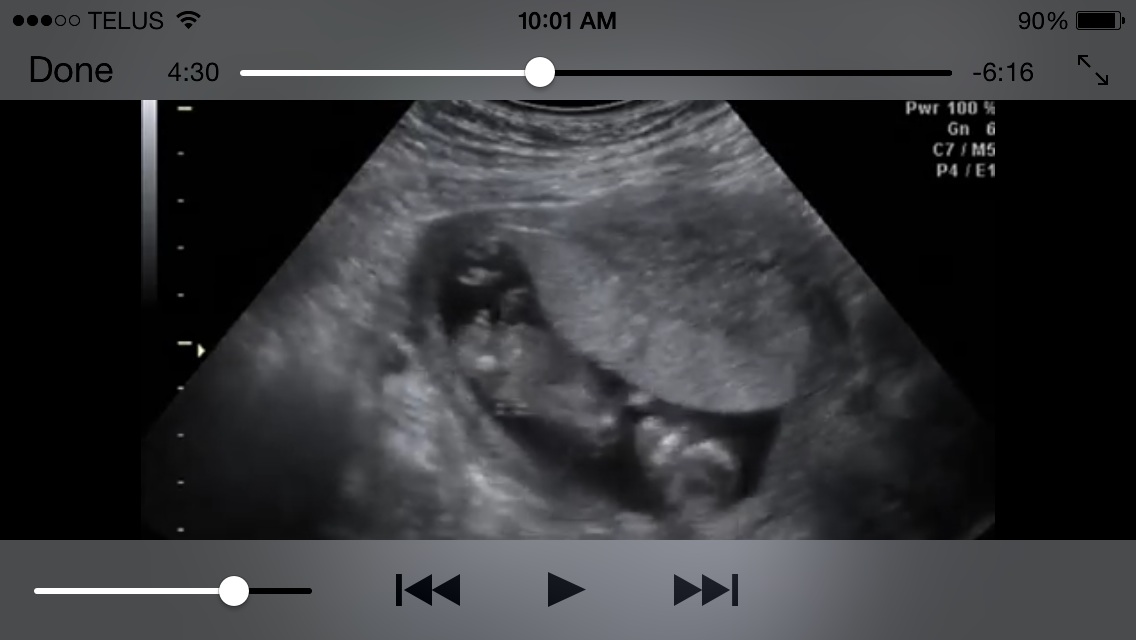

Can you really accurately tell the gender with a 13 week potty shot?

I had an early elective ultrasound I purchased through groupon so my mother in law could see her grandchild since she doesn't live close to us. I read about the nub theory and tried to explain to the tech about it, but she had no idea what I was talking about nor did she want to listen. I tried to get her to get a good profile picture, but right away she seen something in a potty shot and was sure it was a boy. She focused on that pretty much the entire ultrasound. I am confused because I thought that the only way you could tell at this stage was the nub theory because both genders had a protrusion. I was wondering if someone could look at the video I put on youtube and give me your opinion. Ultrasound 4:21 - YouTube

This has been driving me crazy! I have two boys so like I said I have alot of gender pressure! Is this 100% no doubt a boy so I can start shopping for boy stuff to help get me excited about my third boy or should I hold off?